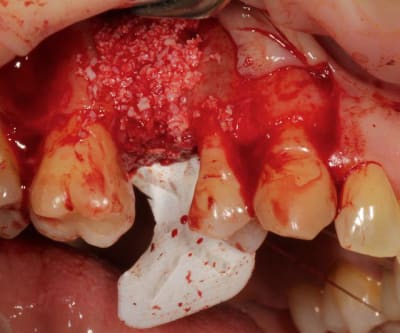

Cas 1-coté gauche maintenant:

photo:

1- ouverture, forme et configuration différente

2- une fois échauffée avec le coté droit, je me dis allez hop, j'attaque une expansion. donc incision crestale avec décharges osseuses

3- mise en place des expanseurs de Mesinger A et B

4-5 notez que l'incision de décharge étant oblique , elle sert également de garde fou contre une éventuelle fracture osseuse. l'os "mobile" vient buter contre l'os "immobile"

> de copaux pour augmenter l'ostéoinduction, conduction, etc...

- tout le monde est d'accord pour provoquer le saignement de la corticale.